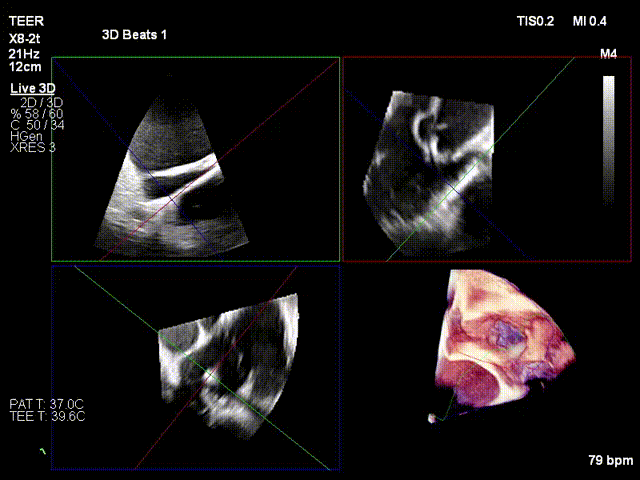

Opening the clamping arms, adjusting the orientation and apposing to the annulus

Closing the clip